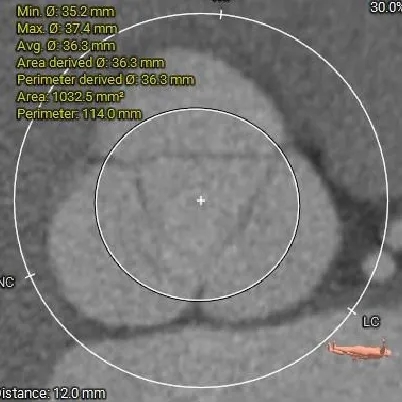

主动脉根部测量

Annulus 27.2mm

LVOT:26.5mm

钙化积分:0

SOV

52.3*54.9*52.1mm

STJ:45mm

AAO:48mm

纯反流三叶瓣,瓣环内径27.2mm

流出道近直筒型

瓣叶无增厚、无钙化

瓦氏窦、STJ、升主明显扩张

瓣上结构测量

瓣上2mm

28.5mm

瓣上4mm

29.9mm

瓣上6mm

30.9mm

瓣上8mm

33.7mm

瓣上10mm

35.2mm

瓣上12mm

36.3mm

瓣上空间逐渐增大,仅瓣上2mm左右可提供锚定